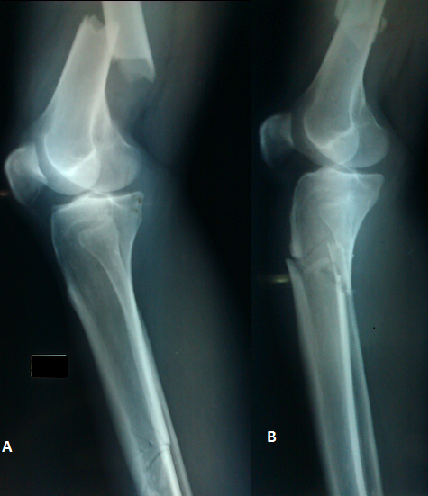

Le genou flottant est une entité lésionnelle décrite pour la première fois en 1975 par Blake et McBride. L'atteinte bilatérale est exceptionnelle. Elle survient pour des traumatismes à haute énergie et est généralement accompagnée d'autres lésions potentiellement vitales. Notre patient a présenté à la suite d'une chute d'une hauteur élevée un traumatisme des deux membres inférieurs. Le diagnostic évoqué cliniquement a été confirmé après bilan radiologique standard. La classification de Fraser permet de distinguer 4 types de genou flottant en fonction du siège des fractures. Le traitement est chirurgical, plusieurs moyens d'ostéosynthèses sont possibles. Chez notre patient nous avant optés vu le siège des fractures pour un enclouage des fémurs (rétrograde) et des tibias. Les complications sont très fréquentes, d'abord d'ordre générales qui peuvent causer le décès du patient (embolies graisseuse, embolies pulmonaires, lésions associées) et locales (infection, cal vicieux, pseudarthroses, raideurs des genoux).